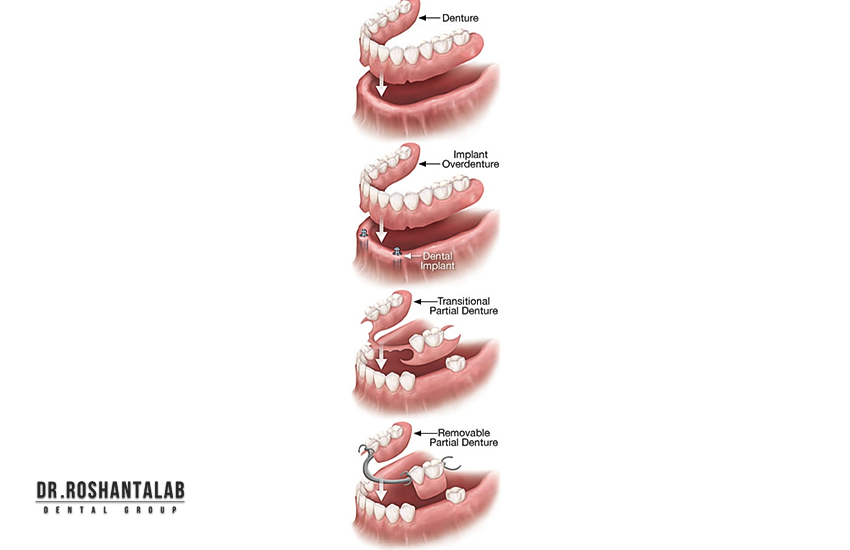

پروتز متحرک به طور کلی دارای سه نوع است:

- پروتز دندانی پارسیل: دندان تکه ای برای پر کردن جای خالی چند دندان از دست رفته در شرایط خاص

- دست دندان کامل: برای افرادی که همه دندان های خود را از دست داده اند.

- پروتز دندان اوردنچر: پروتز کاملی که روی دو پایه دندانی یا چند پایه ایمپلنت قرار می گیرد.

پروتز ثابت دندان به طور کلی دارای سه نوع است:

- بریج دندان: برای پر کزدن جای خالی چند دندان با اتکا به دندان های کناری

- روکش دندان تک واحدی: حفاظت از دندان طبیعی آسیب دیده یا روکش ایمپلنت یک دندان

- پروتز فول فک ثابت: پروتز فول متکی بر 6 الی 8 واحد ایمپلنت در یک فک